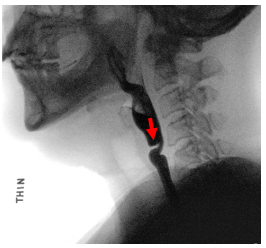

Narrowing can occur both at the top and bottom part of the esophagus. The most common benign type of esophageal narrowing is called a peptic stricture due to acid reflux. These strictures occur in the lower part of the esophagus. Other common types of benign narrowing include esophageal webs or rings, which are thin bands of scar tissue within the lining of the esophagus. Webs are commonly seen in the upper part of the esophagus and rings are commonly seen in the lower part of the esophagus.

Diagnosis of esophageal strictures is made by several evaluations including modified barium swallow study, barium esophagram, and transnasal esophagoscopy.Upper Esophageal Strictures and Webs Treatment

| Upper Esophageal Web | Schatzki Ring |